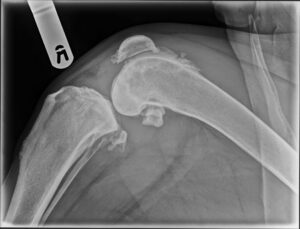

March 2023